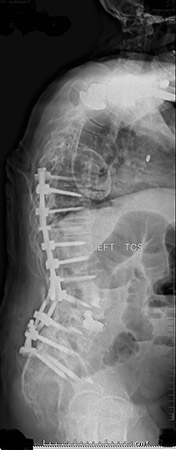

Williams met with Cyrus Wong, M.D., a neurosurgeon on the medical staff at Texas Health Fort Worth and North Texas Neurosurgical & Spine Center, a Texas Health Physicians Group practice. “Michael’s center of gravity was completely off, causing him to lean forward by more than 10 inches every time he attempted to stand or walk,” Wong said.

After undergoing several diagnostic studies, including MRI and CT scans, along with physical exams Williams was diagnosed with scoliosis – a sideways curving of the spine – and flatback syndrome, a condition where the lower portion of the spine loses its normal curvature. “When you have flatback syndrome, you’re in constant pain and disability, you have difficulty standing up or looking straight, and your daily activities are hindered or simply become non-existent,” Wong explained.

Williams underwent pedicle subtraction osteotomy, a complicated surgical procedure that allows a neurosurgeon to strategically reshape the vertebrae to realign a deformed spine. After his spinal procedure, Williams was cared for at Texas Health Fort Worth. “The day after surgery, a nurse came to my room and said I needed to start walking. I told her she’d lost her mind,” Williams said. “Eventually, I got out of bed, but I didn’t feel any pain. I walked up and down the hallways near my room, and I didn’t want to stop.”